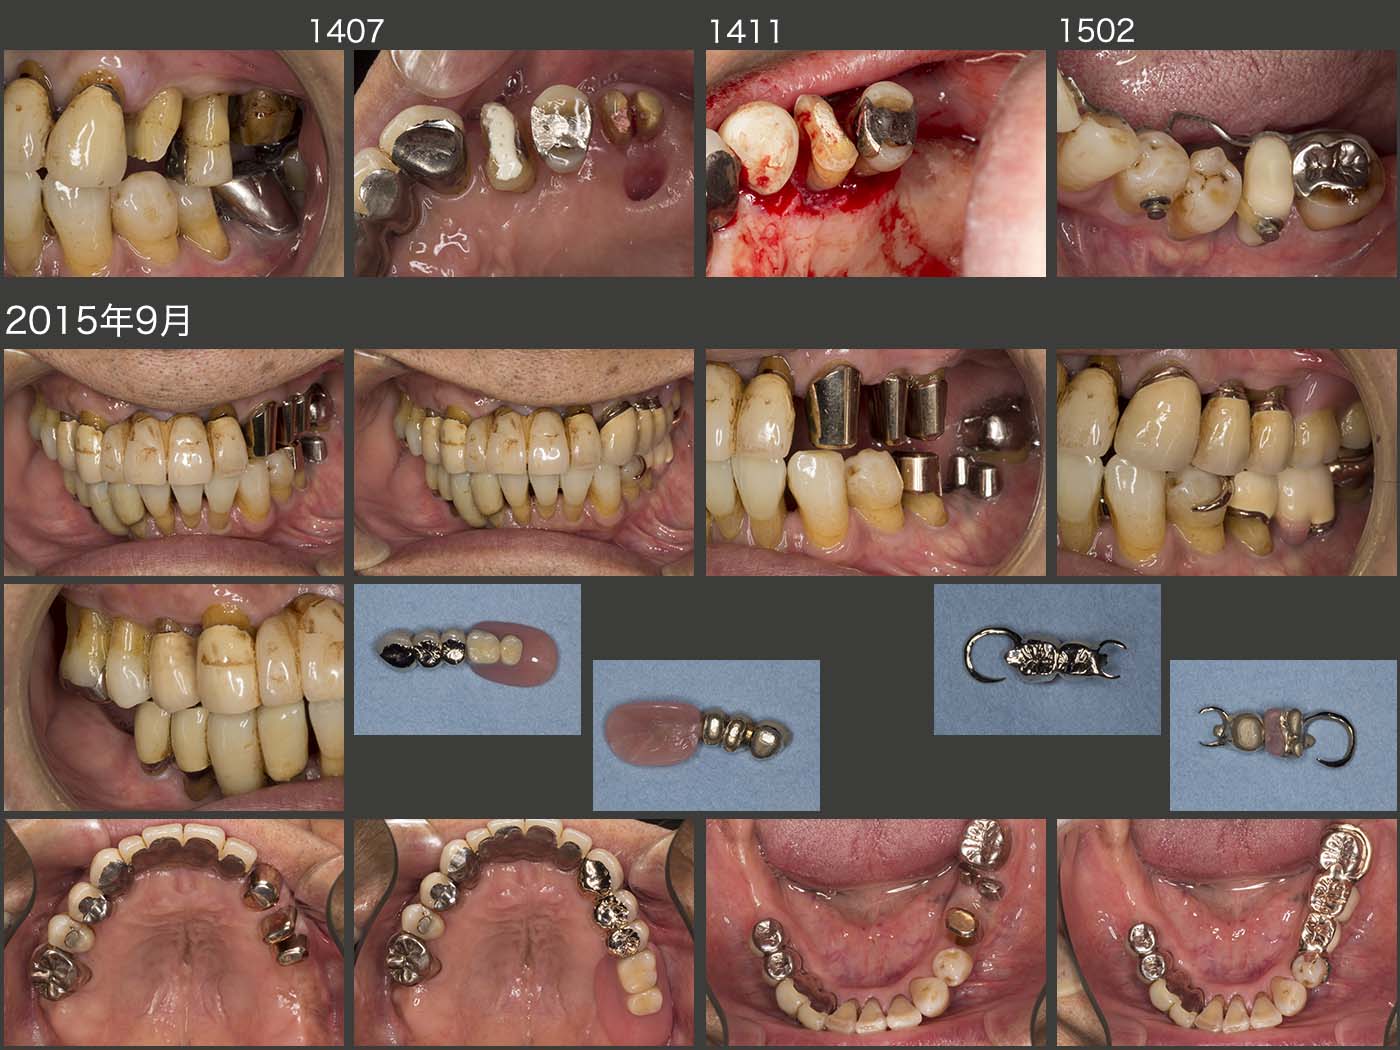

2014年7月,左上4の自然挻出を開始し,11月歯周外科を行った.左上6は暫く様子をみたが,結局抜去した.06年にアップライトを行った,左下5は,舌側に後戻りがみられたため,もう一度アップライトをし直し,抜髄を回避すると同時に,今回は2次固定で対応することにした.

15年9月,左側の上下にコーヌス義歯を製作し,2次固定効果で左側の咬合・咀嚼力に対抗しようと目論んだ